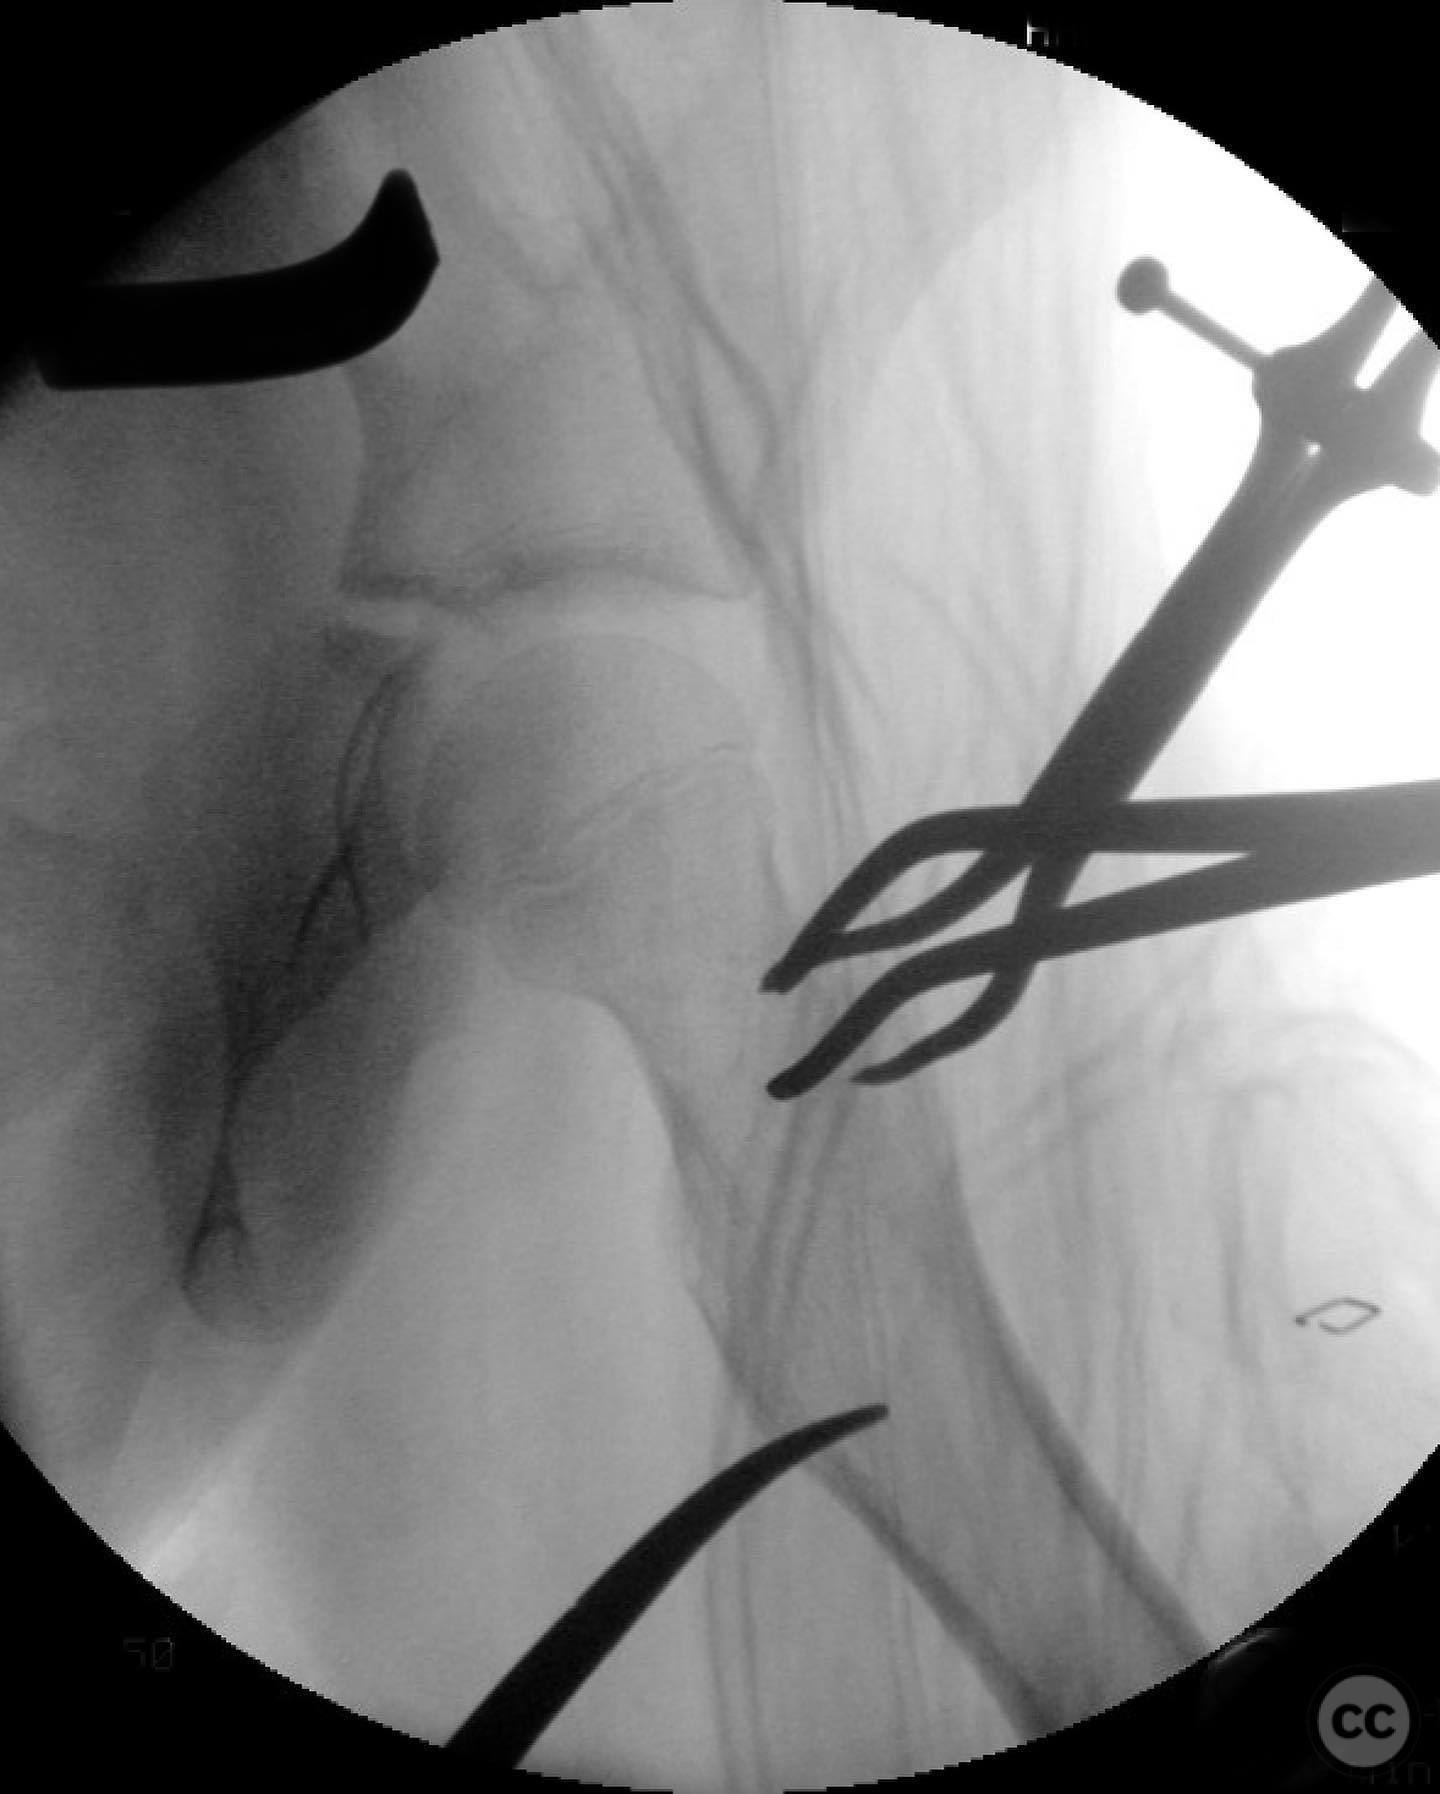

Anatomical surgical approach:  A modified Smith-Petersen approach was utilized, involving an incision along the anterior aspect of the hip, allowing for direct visualization of the femoral neck. Subperiosteal dissection was performed to expose the fracture site without compromising the surrounding musculature. A separate lateral approach was employed for the application of fixation devices.

The surgeon emphasized the importance of achieving a high-quality reduction and stable fixation due to the displacement pattern of the fracture. A meticulous surgical approach was critical to avoid malreduction, which is not well-tolerated in pediatric patients. The modified Smith-Petersen approach provided excellent visualization for anatomic reduction, minimizing soft tissue damage.